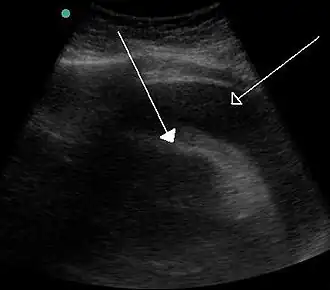

Скопление большого количества жидкости между листками перикарда, видимое при ультразвуковом исследовании. | |

Данное состояние угрожает жизни и без своевременного адекватного лечения может привести к смерти больного. Больной отмечает у себя наличие характерных для сердечной недостаточности жалоб. При разрыве миокарда наблюдается триада Бека, которая включает в себя гипотензию, набухание вен шеи и глухие сердечные тоны. Аускультативно обнаруживаются приглушённые тоны сердца, при ультразвуковом исследовании обнаруживается жидкость между листками перикарда.